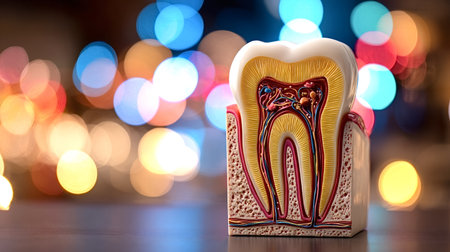

A close-up view of an anatomical model of a human molar tooth's cross-section. The white enamel cap transitions to yellow dentin, revealing the red pulp chamber and root canals within. The surrounding bone structure is depicted with porous texture in beige and red hues. The background is a solid, deep blue.

Tooth model displaying its complex internal structure including enamel, dentin, pulp, and root canals, standing against a vibrant background of colorful, out of focus lights

Dental tooth cross section model showing enamel, dentin, pulp, gum and root structures against a soft colorful bokeh background for oral health education and dentistry study

A detailed dental model illustrates the anatomy of a human tooth highlighting its inner structure including roots and nerves. This model is used for educational purposes in a dental clinic.

This image depicts a detailed anatomical model of a human tooth, showcasing the intricate internal structures, including nerves and blood vessels, essential for educational and healthcare purposes.